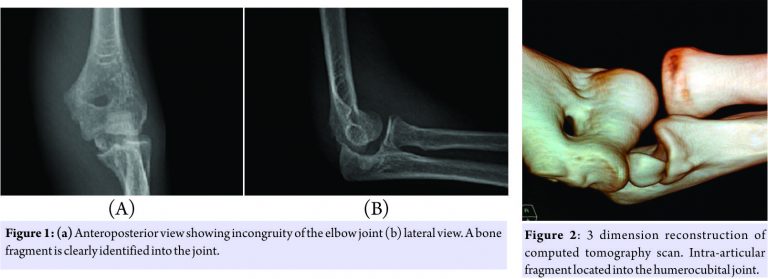

Plain radiographs of the elbow revealed incongruity and increase in joint space of the elbow. The medial epicondyle was not in the anatomic position and a bone fragment was present in the joint (Fig. 1). At this moment, it was obvious that elbow dislocated and reduced spontaneously and medial epicondyle entrapped within the joint. A computed tomography (CT) scan was performed to see if any other pathology was present. Incarcerated medial epicondyle was seen easily in 3 dimension CT scan (Fig. 2).